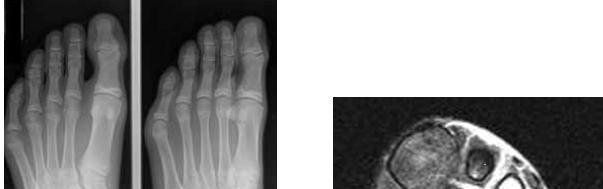

Question 7:

A 54-year-old male with long-standing diabetes presents with a swollen, warm, and erythematous left foot. Radiographs reveal fragmentation and periarticular debris at the tarsometatarsal joints. Which classification system is commonly used to stage the anatomical location of this disease process?

Correct Answer: Brodsky classification

Explanation:

The Brodsky classification describes the anatomic location of Charcot arthropathy. Type 1 is the tarsometatarsal (Lisfranc) joint, which is the most common. Type 2 involves the Chopart/subtalar joints. Type 3A involves the ankle (tibiotalar), and Type 3B involves the calcaneal tuberosity. The Eichenholtz classification describes the clinical and radiographic progression (development, coalescence, consolidation).